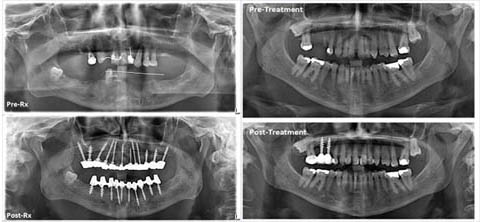

Dental Implants:

Dental implants are artificial teeth replacements that closely resemble natural teeth. They look and feel very natural. They hold crowns just like roots hold natural teeth crowns in place. Implants also can hold bridge work and denture when several teeth are missing. Implants provide much greater stability for more effective eating, speaking and smiling. Unlike a removable denture or bridge, dental implants are firmly fixed to the jaw. Dental implants are made from bio-compatible titanium alloy.

Cortical / Basal Implants (always immediate loading):

Cortical / Basal Implants utilize the basal cortical portion of the jaw bones for retention. These implants are uniquely designed to be accommodated in the basal bone areas. They are anchored to the basal cortical bone, and the crown, bridge or denture is attached immediately or within 3 days. The basal bone is less prone to bone resorption and infections owing to its highly dense structure.